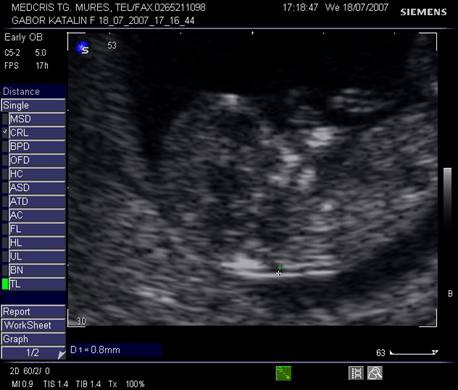

Fig. nr..26. Membre inferioare la fatul de 11 sapt